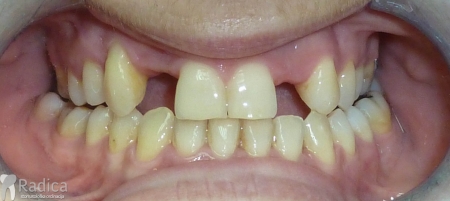

Na sljedećoj slici se mogu vidjeti početak i kraj ortodontske i protetske terapije. Protetske radove radio je dr. Goran Radica.